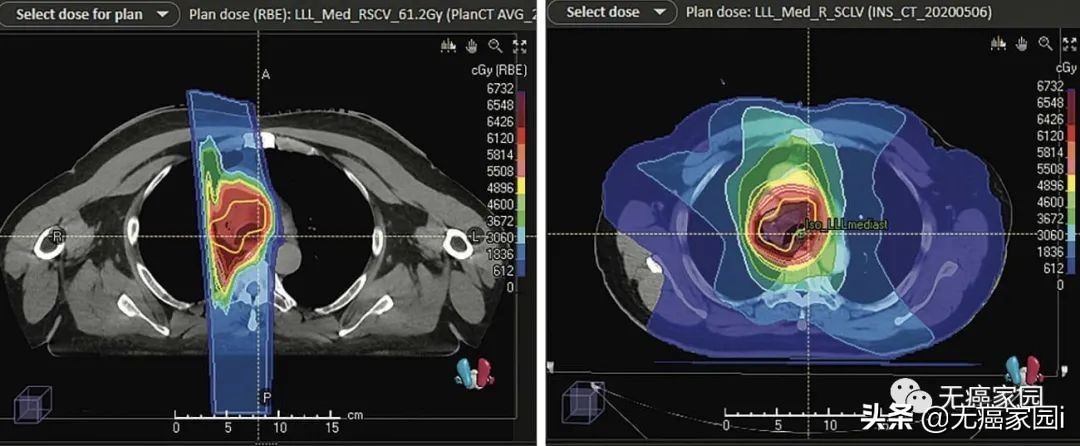

II 期和 III 期非小细胞肺癌

手术通常不是 II 期和 III 期肺癌患者的选择,因为肿瘤可能太大,或者患者可能有医疗问题使他们成为不合适的候选人。在无法进行手术的情况下,采用质子疗法联合化疗进行积极治疗是一种选择。由于具有图像引导和笔形束质子治疗的质子治疗技术减少了对正常组织的辐射暴露,与其他形式的放射治疗相比,质子治疗显著降低了对正常肺、食道、脊髓和心脏的剂量。

与 X 射线/IMRT的辐射相比,质子治疗对肺部和其他附近器官的辐射更少。图像显示了治疗期间暴露于辐射的身体区域

局限期小细胞肺癌 (SCLC)

对于局限期小细胞肺癌患者,质子治疗联合化疗提供了比常规 X 射线辐射毒性更小的积极治疗。这种方案可以使治疗更耐受,副作用更少,如吞咽疼痛和辐射容易诱发肺炎的发生。